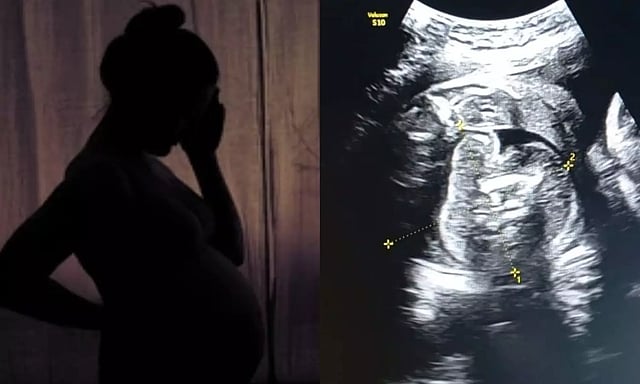

கர்ப்பிணிப் பெண்ணின் வயிற்றில் உள்ள குழந்தைக்குள் வளரும் கரு.. ஆச்சர்யத்தில் மருத்துவர்கள்!

சோனோகிராபி செய்தபோது அவரின் 'கருவில் கரு' வளருவது கண்டறியப்பட்டது.இதுவரை உலகில் வெறும் 200 பேருக்கு மட்டுமே இந்த நிலை உண்டாகியது.

மகாராஷ்டிராவில் புல்தானா மாவட்டத்தின் அரசு பெண்கள் மருத்துவமனையில் 35 வார [9 மாத] கர்ப்பிணியான 32 வயது பெண் ஒருவருக்கு சோனோகிராபி செய்தபோது அவரின் 'கருவில் கரு' [Foetus inside foetus] வளருவது கண்டறியப்பட்டது.

அதாவது பெண்ணின் வயிற்றுக்குள் உண்டாகியுள்ள குழந்தையின் உடலினுள் மற்றொரு முழு வளர்ச்சியடையாத கரு உருவாகி உள்ளது. இதுகுறித்து அந்த மருத்துவமனையின் மகப்பேறு மருத்துவர் பிரசாத் அகர்வால் கூறுகையில், ஆரம்பத்தில் நான் ஆச்சரியமடைந்தேன், பின்னர் கவனமாக ஸ்கேனை மறுபரிசீலனை செய்தேன்.

இது முந்தைய சோனோகிராஃபியில் தவறவிடப்பட்டது. ஏனெனில் இது மிகவும் அரிதான நிலை, இதுபோன்ற ஒரு நிலை இருக்கும் என்று யாரும் கற்பனை கூட செய்ய முடியாது. எனவே, நான் இரண்டு மருத்துவர்களிடம் விரிவான ஆலோசனைக்கு பின் அதை உறுதி செய்தேன் என்று தெரிவித்தார்.

மேலும், குழந்தை பிறந்த பின்னரே இந்த நிலை பெரும்பாலும் கண்டறியப்படும். ஆனால் இப்பெண்ணுக்கு பிரசவத்துக்கு முன்னரே கண்டறியப்பட்டுள்ளது.

இது 5 லட்சத்தில் ஒருவருக்கு மட்டும் நிகழக்கூடிய அரிய வகையான மருத்துவ நிலை. இதுவரை உலகில் வெறும் 200 பேருக்கு மட்டுமே இந்த நிலை உண்டாகியது. அதில் இந்தியாவில் 15-20 பேரில் மட்டுமே இந்த நிலை பதிவாகியது என்று தெரிவித்தார்.

இந்த நிலைக்கான சரியான காரணம் முழுமையாக புரிந்து கொள்ளப்படவில்லை, ஆனால் இது ஒரே மாதிரியான இரட்டையர்களின் வளர்ச்சியின் போது நிகழும் ஒழுங்கின்மையின் விளைவு என நம்பப்படுகிறது.